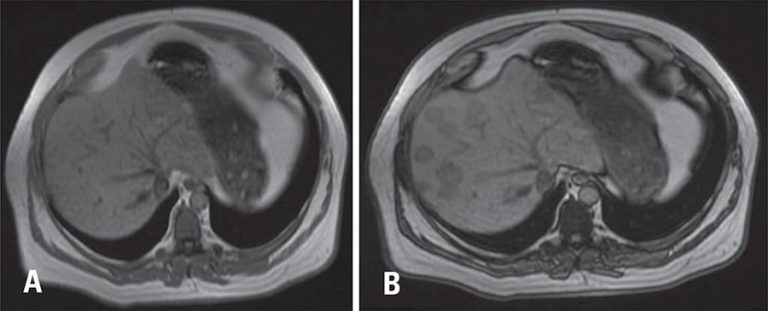

Paciente de 56 anos em investigação de lesão expansiva lítica no clivus, posteriormente caracterizada como cordoma condroide, confirmado pela histopatologia, após ressecção da lesão, foi encaminhado para realizar tomografia computadorizada de abdome devido a quadro de desconforto abdominal, para pesquisa de metástases.

A fase sem contraste revelou múltiplas formações nodulares hipoatenuantes de tamanhos diversos, a maior com 3,2cm. Nas fases contrastadas, as lesões apresentavam realce similar ao parênquima adjacente, porém sem significativo efeito de massa ou sinais de agressividade, uma vez que estruturas vasculares (veias hepáticas e ramos portais) atravessavam tais lesões, sem deslocamentos ou invasão. O conjunto dos achados, embora não patognomônicos favorecia a hipótese de esteatose nodular multifocal.